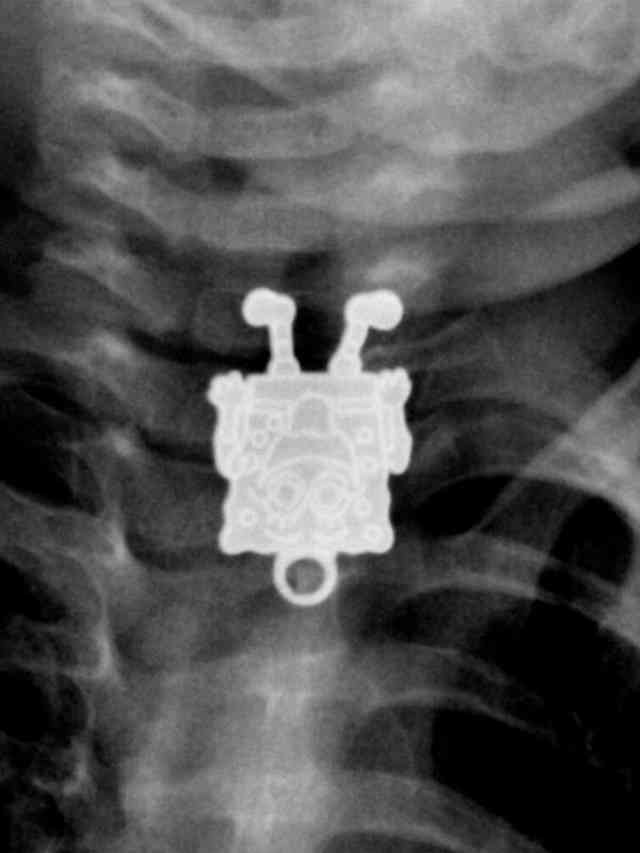

SpongeBob SquarePants Went Diving Too Far

It isn’t clear how he managed to do it, but Mr. Squarepants’ latest adventure looks as though it is taking place inside the abdominal area of a child. The spongy fry cook, whose expertise seems to be getting into trouble in his hometown of Bikini Bottom, is still able to smile even while being digested with stomach acid.

This trip to the hospital might’ve been a grand adventure for SpongeBob, but probably not as much of a thrill for the parents who had to drive their sick kid out to A&E. That’s why reading choking hazard warnings is advisable to all of those that have little ones in their care.